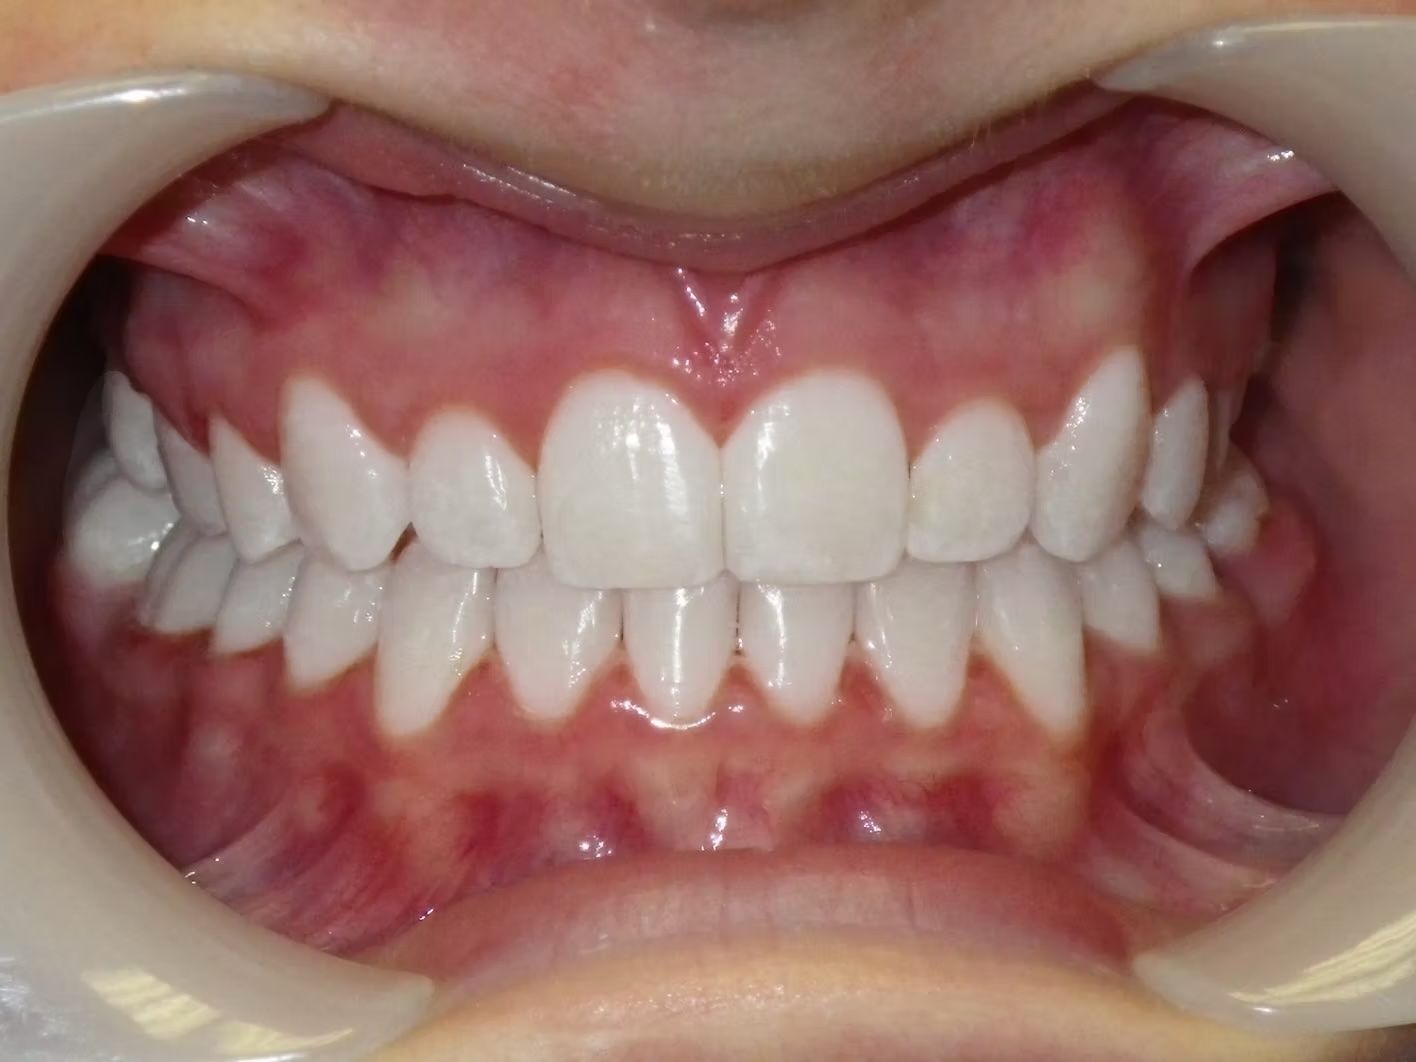

AUSTIN

Austin didn't like that his upper teeth fit behind his lower teeth. (He had an anterior crossbite). When this happens there are usually 3 ways to correct it. One way is just to move the top teeth forward, another is to take out teeth to help correct the crossbite, and sometimes and thankfully less common is to have jaw surgery to correct a skeletal size discrepancy between the top and bottom jaw. Dr. Bret was able to align Austin's teeth and correct his cross bite without taking out any teeth. Austin was super happy and loves his new smile.